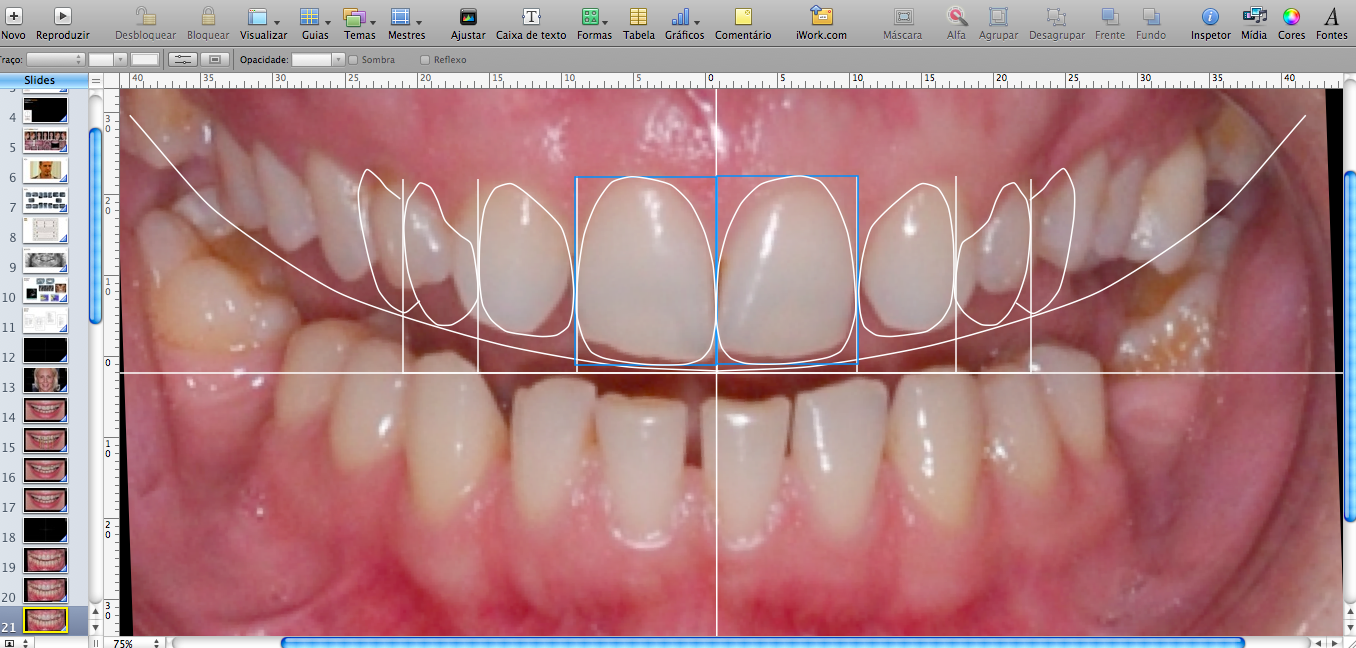

Consiste em um ensaio fotográfico prévio onde são realizados imagens digitais em alta resolução do sorriso, dentes e face do paciente. Essas imagens são inseridas em um software e analisadas minunciosamente.

Após analise fotográfica, um projeto de um novo sorriso é desenhado, individualmente, em computador e analisado digitalmente, podendo ser compartilhado e visualizado pelo paciente e dentista antes de ser posto em prática.

O grande objetivo do DSD é criar um design de sorriso que esteja de acordo com as necessidades funcionais, estéticas e até emocionais do paciente, como ter um sorriso mais delicado, mais extrovertido ou mais intenso. Palavras que se materializam na transportação virtual do sorriso, antecipando o resultado esperado.